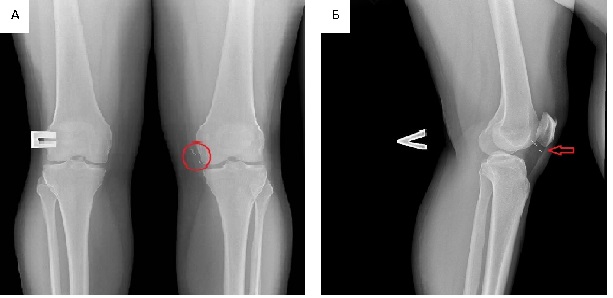

X-ray examination of the knee joints: moderate narrowing of the joint space in the frontaland lateral projections. Intercondylar eminences sharpened. In soft tissues of the left knee joint mediallyand below the patella, an X-ray-positive, thin, fragmented formation 2 cm–2.5 cm long was detected. Conclusion: moderate signs of deforming gonarthrosis, an X-ray positive, fragmented foreign body in the soft tissues of the left knee joint (Figure 1).

Fig. 1. X-ray of the left knee joint in frontal (A) and lateral (B) projections. Note: medially and below patella an X-ray-positive, thin, fragmented formation 2 cm–2.5 cm long is determined (the area of the foreign

body is encircled and indicated by arrow).